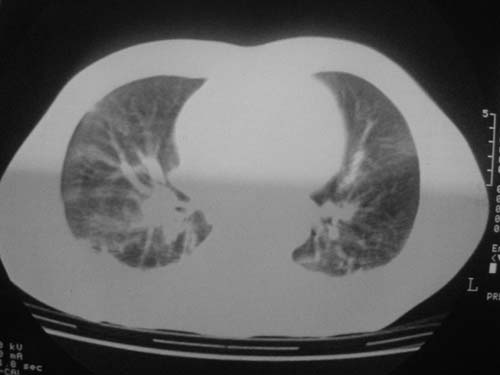

1)双侧创伤性湿肺。2)双侧胸腔积液。

跟主治医生讨论病例

结果:病人刚入院水电解质紊乱,治疗期间大量输液,而且速度较快,正如4.5楼那样说的引起肺水肿,对症治疗后病情好转,